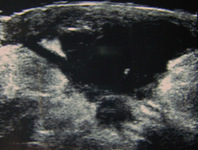

Ultrasound image showing a well-circumscribed hypoechoic breast abscess

From the collection of Holly S. Mason, MD, Tufts University School of Medicine, MA